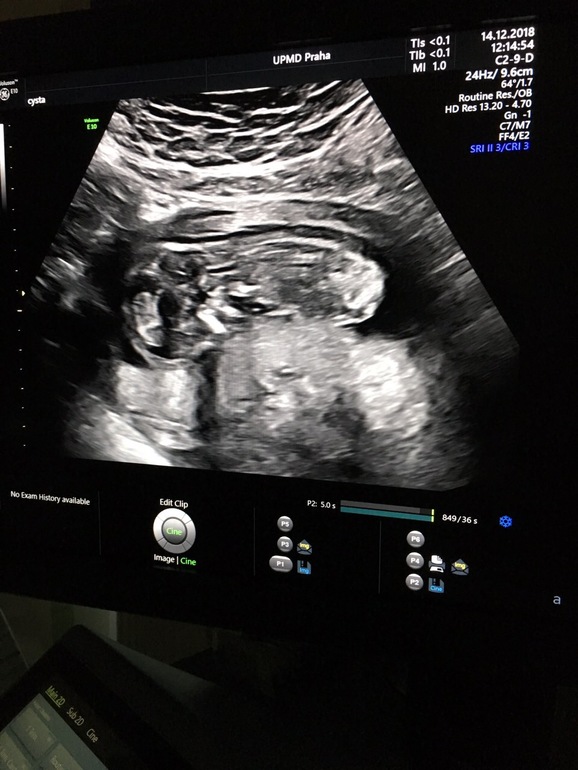

Скрининг 12.6

Была на скринине все у нас отлично Слава Богу, срок поставили 13-3, опережаем чуть чуть. Предположили девочку, я очень хотела мальчика, но самое главное здоровый малыш. Девочки у вас у всех совпал пол который вам сказали на первом скрининг?

вот первая картинка 12 недель,следующие уже 17,,,